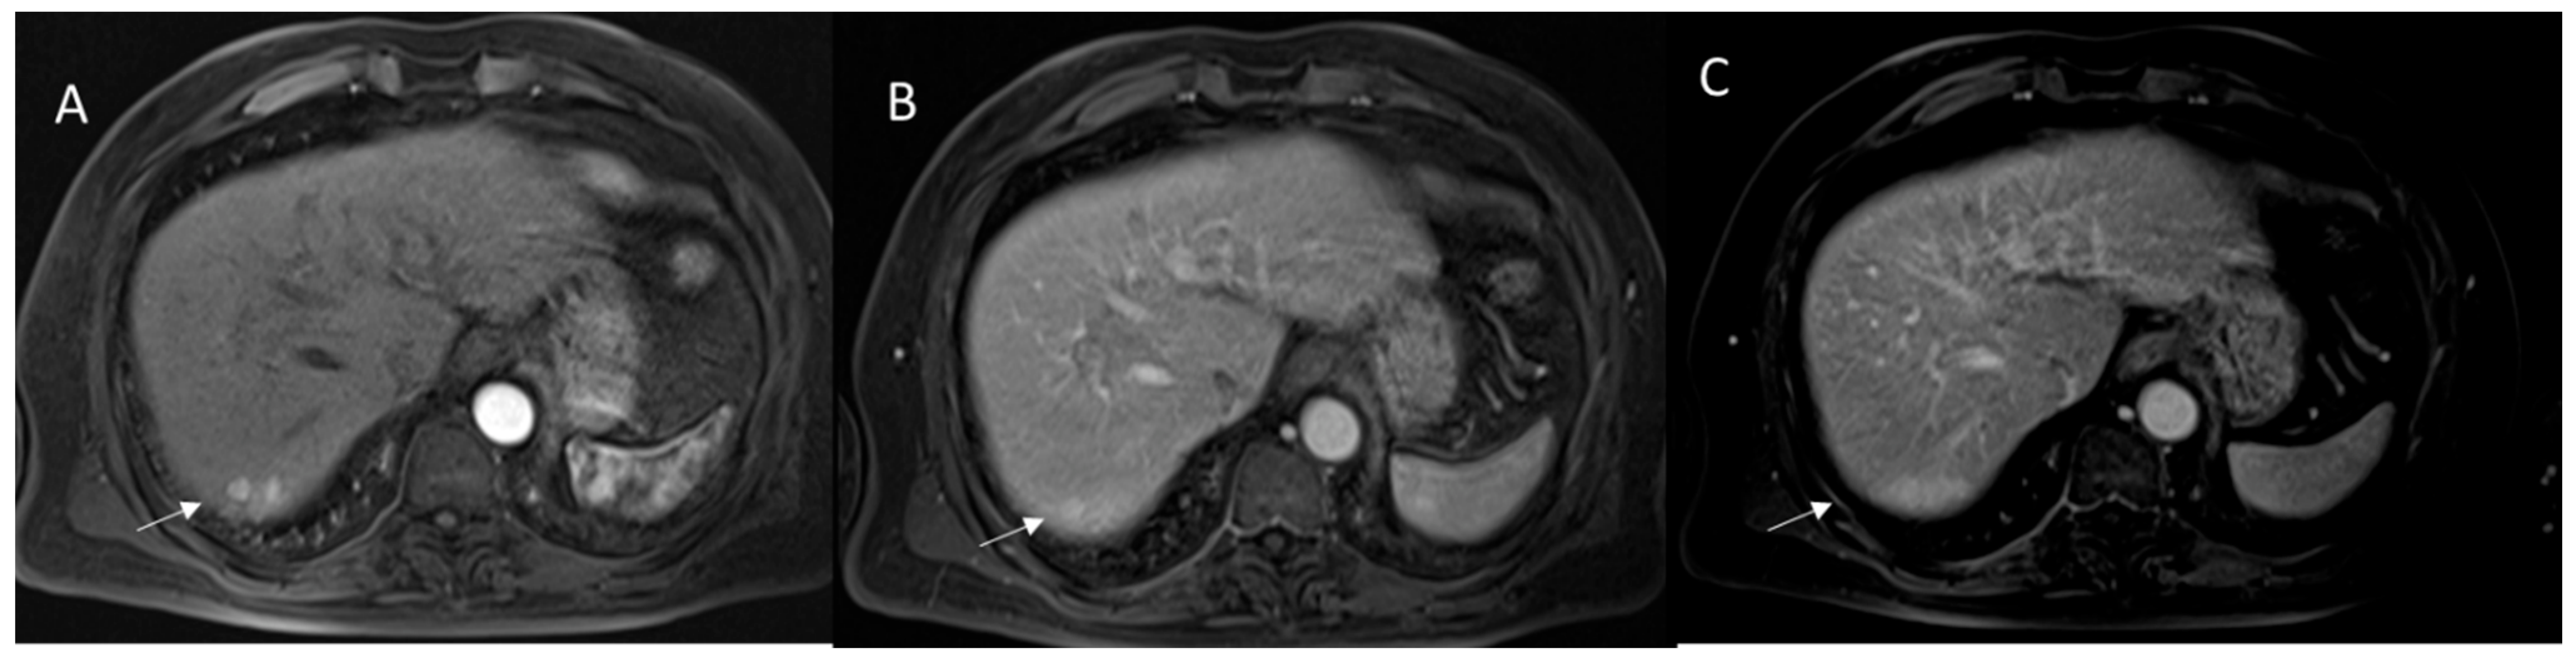

2.2.4. Ancillary Features

2.2.5. LR-M Category